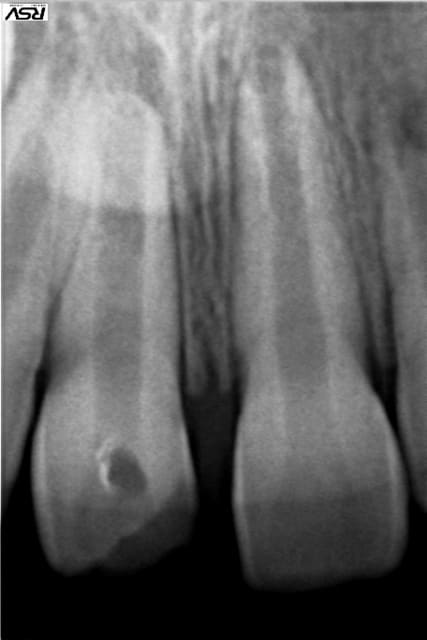

Cas clinique loin d'être parfait et je n'en était pas très fier :

12 ans

Traitement réalisé au MTA, j'ai merdé dans le placement du MTA comme on peut le voir sur la radio...

Radio 1 an post op : cicatrisation osseuse, plus de symptômes et pas d'inflammation particulière autour du MTA. Les parents sont prévenus que si ça pose problème on y retourne en chir.

PS : Ce n'est pas moi qui gère la prothèse, les parents n'ont pas donné suite au traitement coronaire proposé par leur dentiste... dommage